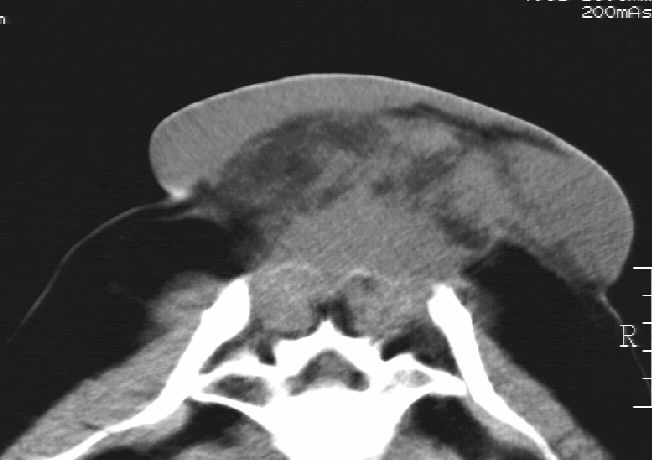

刘某,女,44岁,生第一胎时发现腰背部肿块,黄豆大小,至今17年,呈逐年增大,现行ct检查如下,敬请各位指点。

病史:女,44岁,腰背部肿块,黄豆大小,17年,呈逐年增大。

ct示:骶骨见软组织密度影,似见细条状,或花边状高密度影,考虑不典型钙化灶,向后生长,超出皮肤,可见骶骨破坏,第5幅ct图似与骶管相通。

诊断:脊索瘤

病程长,生长慢,肿块巨大,考虑神经纤维瘤,脂肪密度可以用肿瘤生长过程中包裹入皮下脂肪解释。